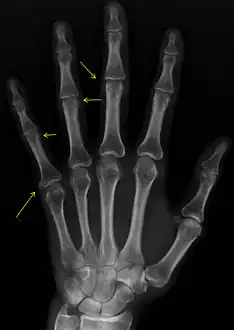

X-ray of subtle calcifications in CREST syndrome